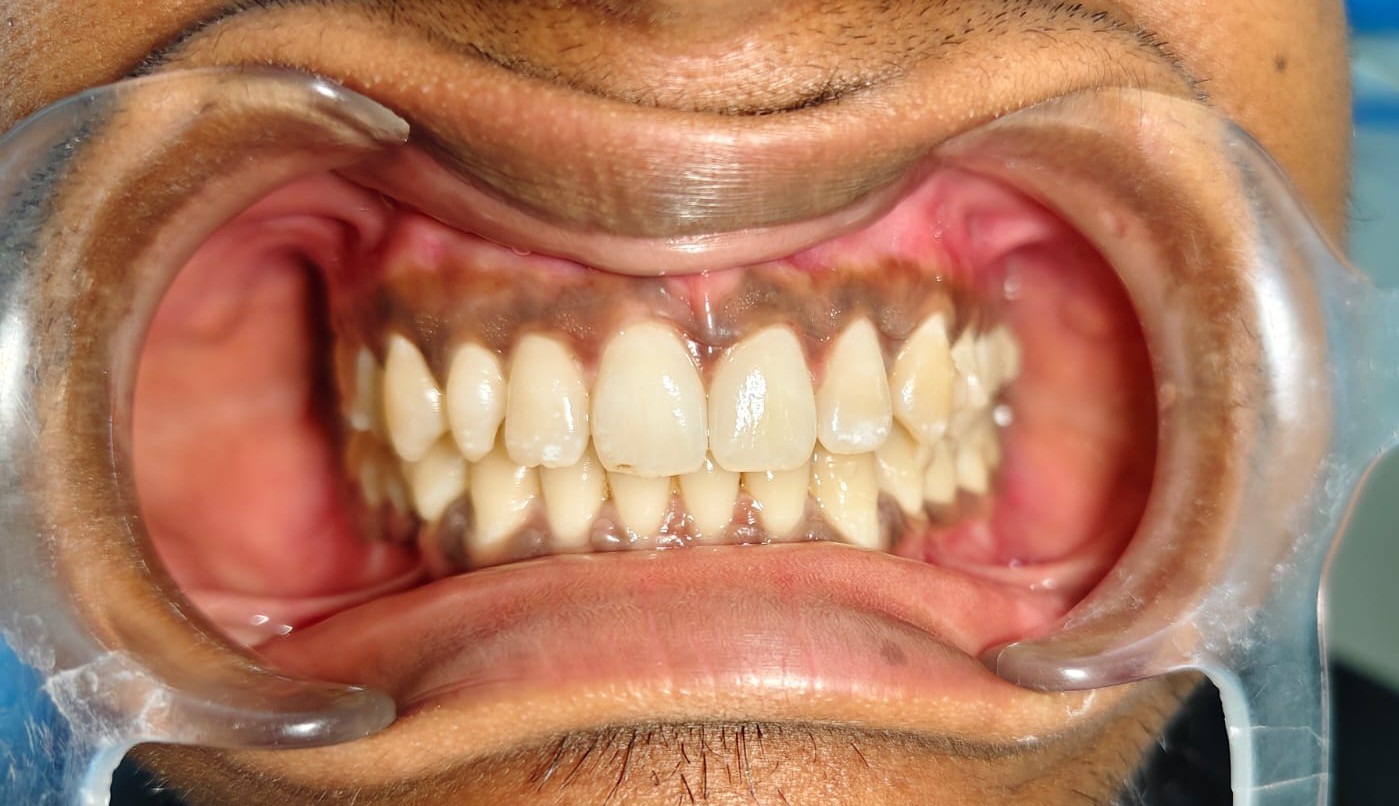

Sairam dental care located in Dharmapuri, with Leading Dentist In Oddapatti, is the Dental Hospital with exclusive root canal, Braces & Invisalign center. Led by renowned Drs Raghuraaman ( Periodontist) and Nivetha Raghuraaman ( Orthodontist) Sairam dental care offers gum treatment with expertise in laser, root canal treatment and digital smile correction with advanced technology aim to focus on aesthetics, comfort and precision. The clinic also specializes in Invisalign treatment, digital smile makeover, laser gum care, dental implants, root canal therapy, extractions and full-mouth rehabilitation blending compassionate care and clinical excellence.